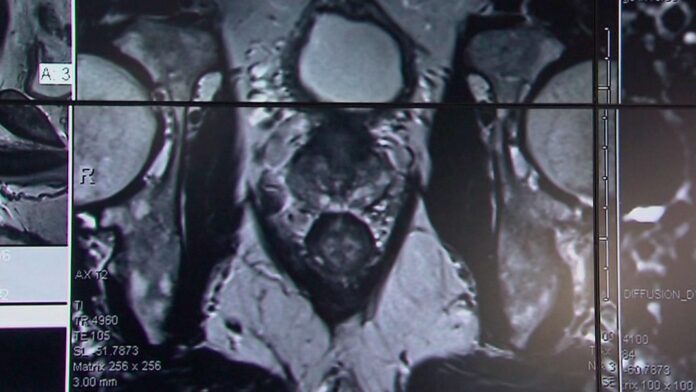

Ahora, dice, los médicos disponen de más herramientas, como la resonancia magnética y las pruebas genéticas, que pueden ayudar a orientar el tratamiento y minimizar el sobrediagnóstico.

Cuando ingresaron, los hombres fueron asignados aleatoriamente a uno de los tres grupos siguientes: seguimiento activo, es decir, análisis de sangre periódicos para vigilar sus niveles de PSA; radioterapia, que utilizaba bloqueantes hormonales y radiación para reducir el tamaño de los tumores; y prostatectomía, o cirugía para extirpar la próstata.